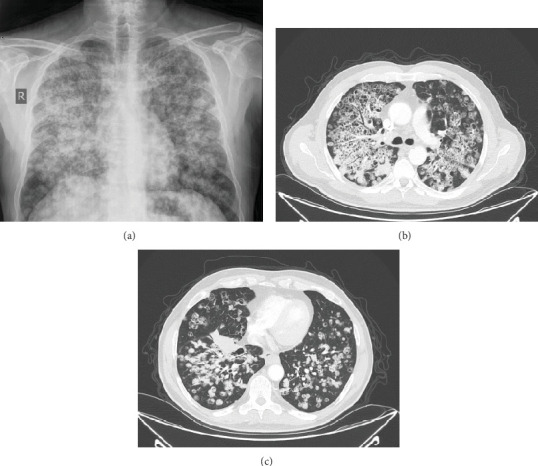

Introduction: Lung cancer is the leading cause of cancer-related mortality, with non-small cell lung cancer (NSCLC) accounting for 85% of cases. Lung adenocarcinoma, the most common subtype, can mimic benign conditions like pneumonia, lung abscess, and interstitial lung disease due to its varied radiologic presentations and associated inflammation and fibrosis. This similarity can delay diagnosis, emphasizing the need for imaging and histopathological confirmation. Case Presentation: A 58-year-old male with a significant smoking history, hypertension, and GERD presented with a 5-month history of episodic epigastric pain, exacerbated by heavy meals, along with progressive respiratory symptoms, including shortness of breath, dry cough, and a 20-kg weight loss over 3 months. Upper endoscopy revealed gastric ulcers, a hiatal hernia, esophageal mucosal changes consistent with GERD, and Helicobacter pylori infection on biopsy, which was treated with triple therapy, resolving his gastrointestinal symptoms. However, his respiratory symptoms worsened, with increased dyspnea at rest, pleuritic chest pain, and a persistent cough. Chest CT showed multiple cavitating lung nodules, architectural distortion predominantly in the upper lobes, a large irregular lesion in the right lower lobe, and enlarged paratracheal, subcarinal, and distal paraesophageal lymph nodes. The patient was transferred to our facility for further evaluation. Whole-body CT revealed widespread bilateral cavitary lesions, lymphadenopathy, and a small hiatal hernia. Bronchoscopy with biopsy confirmed metastatic lung adenocarcinoma, with histopathology showing moderately differentiated adenocarcinoma, positive for TTF-1 and Napsin A and negative for PAX8. Cytology from bronchoalveolar lavage also confirmed malignancy, and PD-L1 immunostaining showed weak positivity in 15%-20% of tumor cells. The patient was diagnosed with metastatic lung adenocarcinoma and initiated on carboplatin and pemetrexed chemotherapy. Molecular testing was planned, and he was discharged for follow-up care. Conclusion: Our case of a 58-year-old male with cavitating lung nodules, significant weight loss, and progressive respiratory symptoms, initially misattributed to gastrointestinal disease, highlights the diagnostic complexity of lung adenocarcinoma. The biopsy-confirmed diagnosis of metastatic adenocarcinoma underscores the need for clinicians to maintain a high index of suspicion for malignancy in patients with atypical or nonspecific presentations. Early tissue diagnosis is crucial for timely treatment and improved outcomes, especially in cases involving cavitary lesions or persistent, unexplained symptoms.